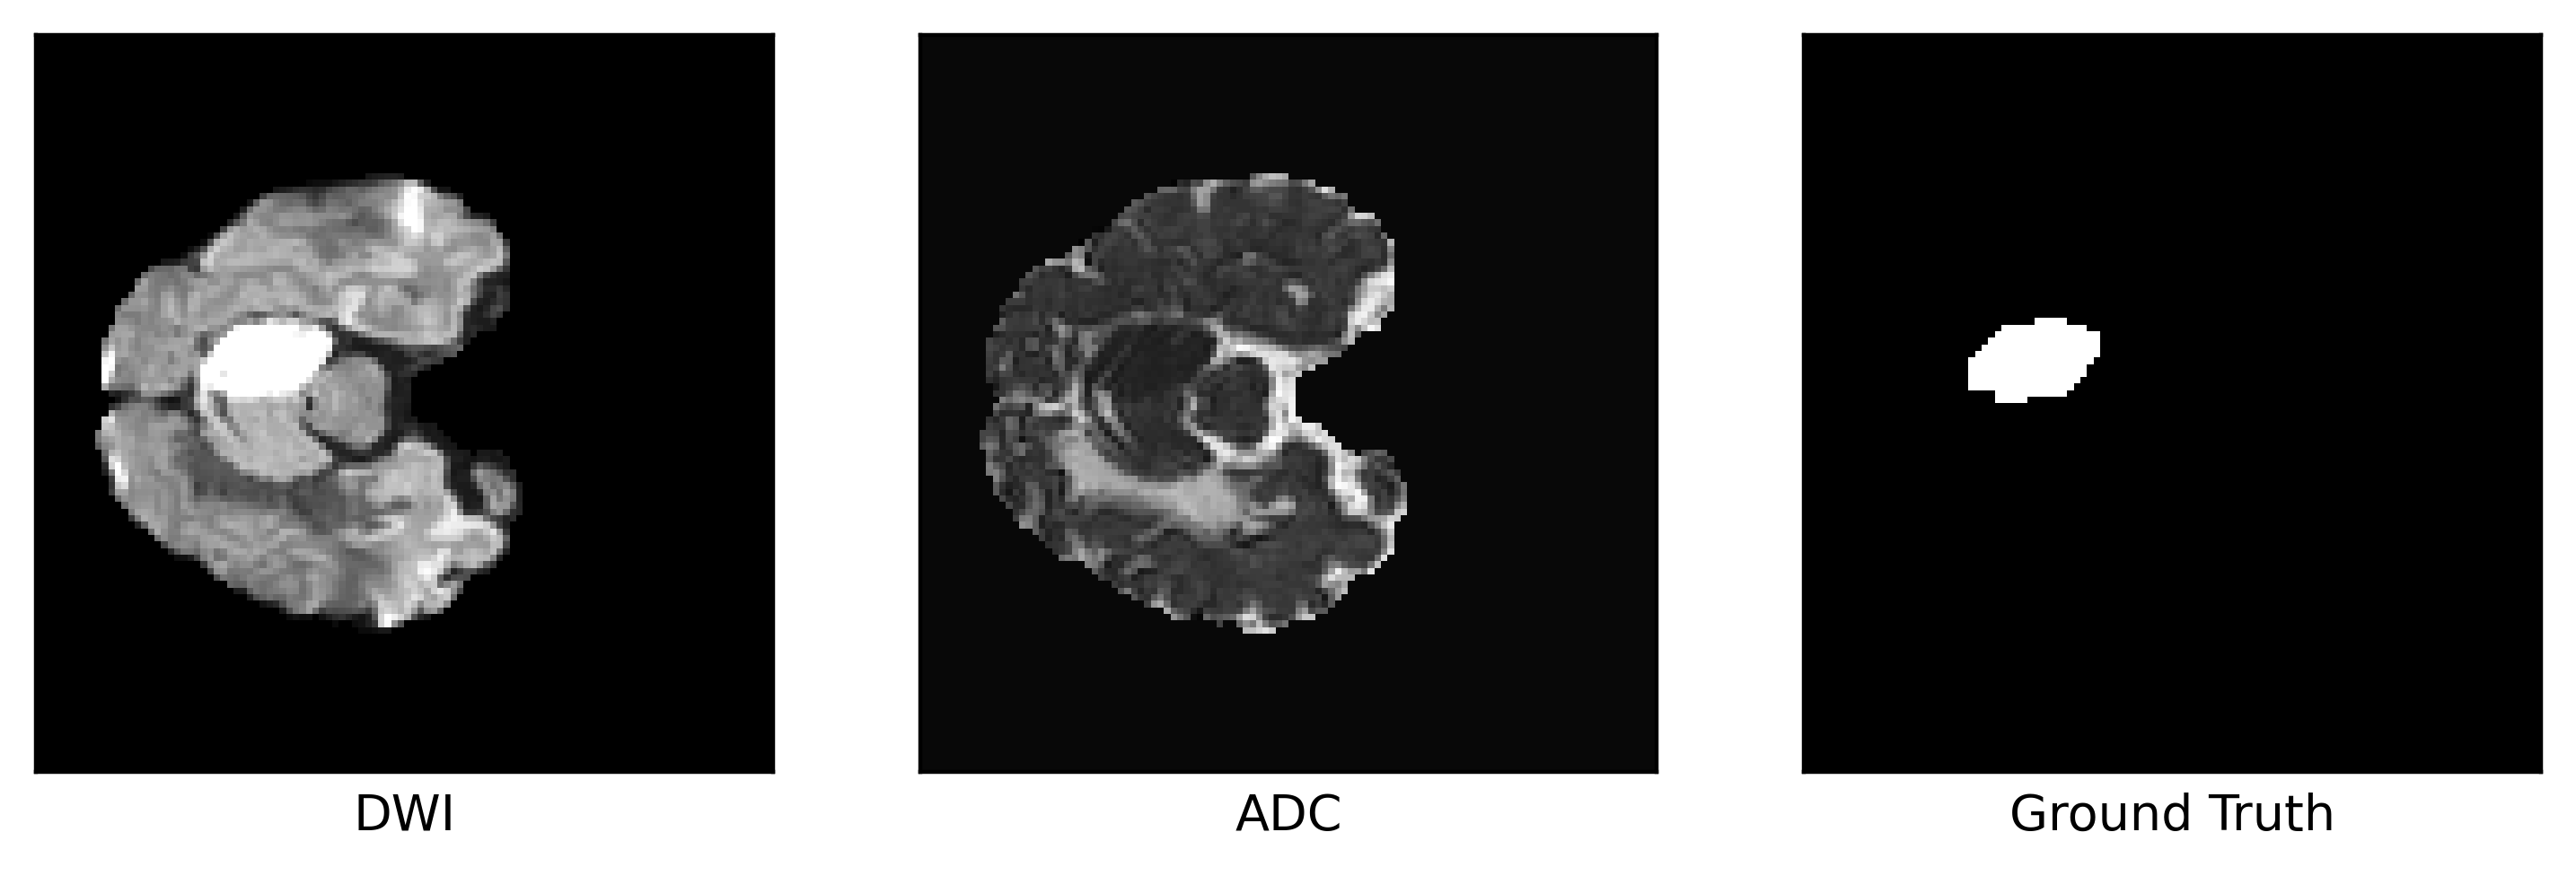

Stroke patients typically undergo neuroimaging techniques to distinguish between ischemic and hemorrhagic strokes. This differentiation can be achieved through magnetic resonance imaging (MRI) and computed tomography (CT), each offering distinctive insight into the condition of the brain [31]. MRI offers excellent soft tissue contrast for the brain, and when diagnosis is uncertain, it can be more informative than CT [47, 16, 28], providing information on stroke location [29], timing [6], and mechanism [112]. Diffusion-weighted imaging (DWI) and perfusion-weighted imaging (PWI) within the MRI protocol offer valuable information on the extent and impact of stroke on brain tissue [94]. Refer to Figure 1 for an illustration showing a stroke infarct sample in two distinct magnetic resonance modalities along with the corresponding annotation. Additionally, refer to Figure 2 for CT images accompanied by corresponding annotations.

Figure 1: Sample of stroke infarct on Diffusion-weighted and Apparent diffusion coefficient MRI with the annotation, from [40]. The infarct appears hyperintense in DWI and hypointense in ADC.